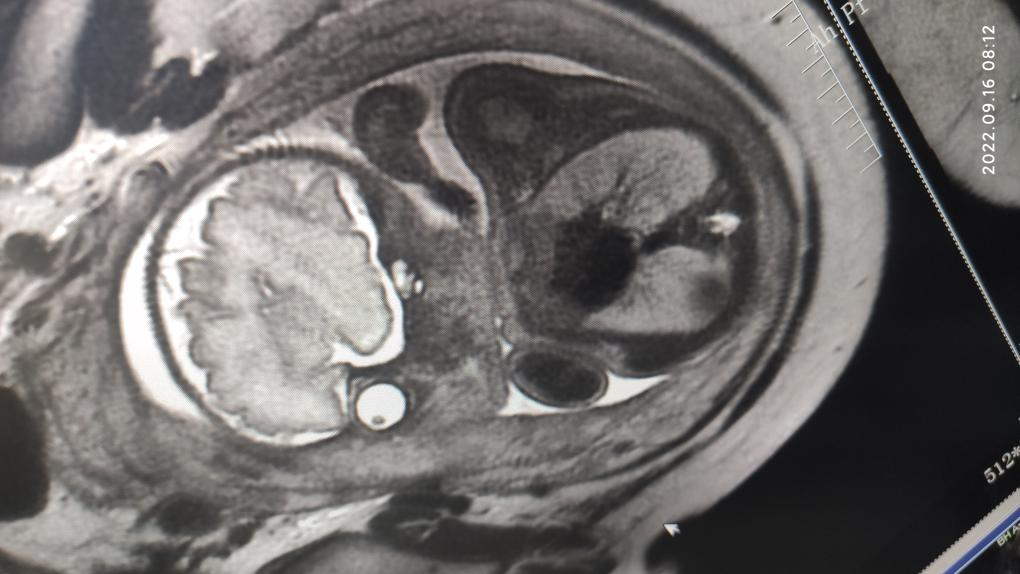

(腹部超高时间分辨率动脉期多时相扫描)

联影磁共振怎么样开启高精度诊断新模式!联影光梭3.0T磁共振落户周口市中心医院_https://www.jmylbn.com_新闻资讯_第6张

此外,联影智能光梭uMR790 3.0T 磁共振具有丰富的扫描检查模式,能够完成包括神经系统、胸部、腹部、盆腔、心血管、骨骼关节、软组织、乳腺等全身各部位磁共振检查,并且能够完成以前不能进行的胸部等部位磁共振检查。不同序列能够对组织结构和病灶进行多角度、多方位观察,利于病灶定性分析,同时,能够大大提高较多、较小病灶的检出率,做到早发现、早治疗、提升患者后续生活质量。并且可以大量应用于全身各部位的功能成像,能够详细地观察人体各器官结构和病变的形态学变化,有利于疾病的诊断和鉴别诊断。

周口市中心医院磁共振室现已全面开展各项磁共振高级功能成像(包括SWI、PWI、BOLD、MRS、DTI等)、胎儿、乳腺、心脏、颞颌关节、动脉高分辨血管壁分析以及周围神经等检查,陆续开展磁共振介入和磁共振高级科研临床应用。磁共振功能成像广泛应用于临床各科,如神经内外科、肝胆内外科、心内科、小儿科、妇产科、泌尿科、肿瘤内外科等临床各个学科,这些极其优秀的特色MR成像技术,大大提高临床疑难疾病的诊断符合率,更有助于临床医生更准确有效及时的治疗,让患者得到更优质的康复。比如,DTI用于脑肿瘤对正常白质纤维束的侵占,术前和术后对于治疗效果的评估,可以更准确地反映白质纤维束的空间走向。在心血管领域突破了心脏禁区,可全面评估,心脏大血管解剖结构成像、心肌功能分析等全方位的检查研究,大大方便了中老年心脏病患者。在体部领域实现了肝脏三维容积超快速多期动态增强检查,可以敏感发现早期微小肝癌,不会遗漏边缘部位和微小病变。充分利用GE 3TMR“乳腺微观成像”高分辨展示乳腺结节、导管及淋巴结转移;“磁共振灌注成像”界定急性脑梗塞的缺血半暗带;“波谱成像”能真正在活体(病人)上分析化学成分。因此,努力提升MRS、SWI、DTI、PWI、CEMRA、腹部MR平扫及增强等MR功能成像业务,极大程度地避免了病人要到外地就医问题,也进一步提升了科室技术水平,并能获得良好的社会效益和经济效益。MR引导下穿刺活检及介入治疗。